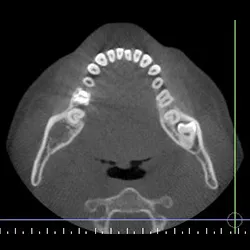

Cone Bean Computer Assembled Tomography

Our office uses the most advanced technology to treat our patients in the most effective way. We use the award-winning i-CAT 3D FLX Cone Beam Computer Assembled Tomography (CBCT) imagining system to acquire the most diagnostic image with less radiation than the average panoramic or traditional x-ray. The dose from this imaging system is 80-95% less than a medical Computed Tomography. With an extremely short scan, typically within five seconds, we can obtain enough data for a comprehensive diagnosis.

The type of radiation produced by the i-CAT is no different than that produced by any other x-ray machine. But with less radiation, one i-CAT scan can replace all of traditional images like panoramic, a lateral cephalogram (head film) and various periapical x-rays in just one click.

i-CAT 3D imaging provides exceedingly beneficial information about the following:

• Less radiation

• More details

• 3D image system

• Precise location of impacted teeth

• Precise measurement of implant placement

• Bone loss visualization

• Medical findings